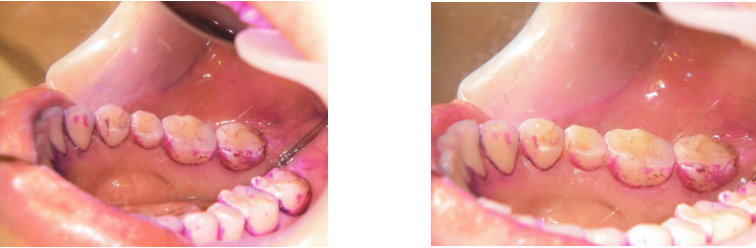

最新口腔ケア情報5つ 乳酸菌サプリ 抗菌グッズで口内環境改善 Lee

噂のくわえるだけのマウスピース型電動歯ブラシを使ってみた 神谷町デンタルクリニック